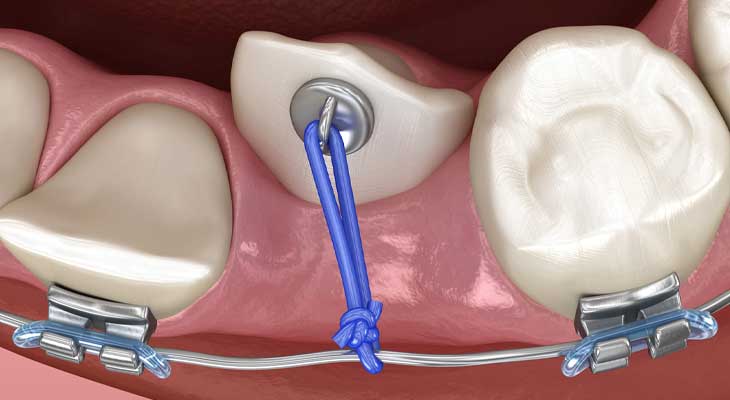

جراحی یک بخش مهم از فرآیند است. هدف از جراحی، اکسپوز کردن دندان است. یعنی نمایان کردن تاج دندان نهفته. این یک عمل سرپایی و ساده است.

جراح با برداشتن لثه و استخوان روی دندان، آن را در دسترس قرار میدهد. سپس یک نگین یا براکت ارتودنسی به آن متصل میکند. یک زنجیر یا سیم نازک به این براکت وصل میشود. انتهای دیگر زنجیر در اختیار متخصص ارتودنسی قرار میگیرد. این فرآیند به درمان چرخش و جابجایی دندان کمک زیادی میکند. همکاری این دو متخصص بسیار حیاتی است.

بعد از جراحی، کار ارتودنسی شروع میشود. متخصص با استفاده از نیروی کنترل شده، دندان را حرکت میدهد. این نیرو از طریق زنجیری که به دندان متصل است، اعمال میشود.

براکت یا نگینی که روی دندان نیش نهفته چسبانده میشود، معمولا یک قلاب یا حلقه کوچک دارد. به این قلاب یک زنجیر یا سیم نازک متصل میشود تا بتوان نیروی لازم برای کشیدن دندان را از طریق آن اعمال کرد. سایر براکت ها دارای شیاری برای قرار گرفتن سیم اصلی ارتودنسی هستند. کش ارتودنسی نیز برای اعمال نیرو استفاده میشود.